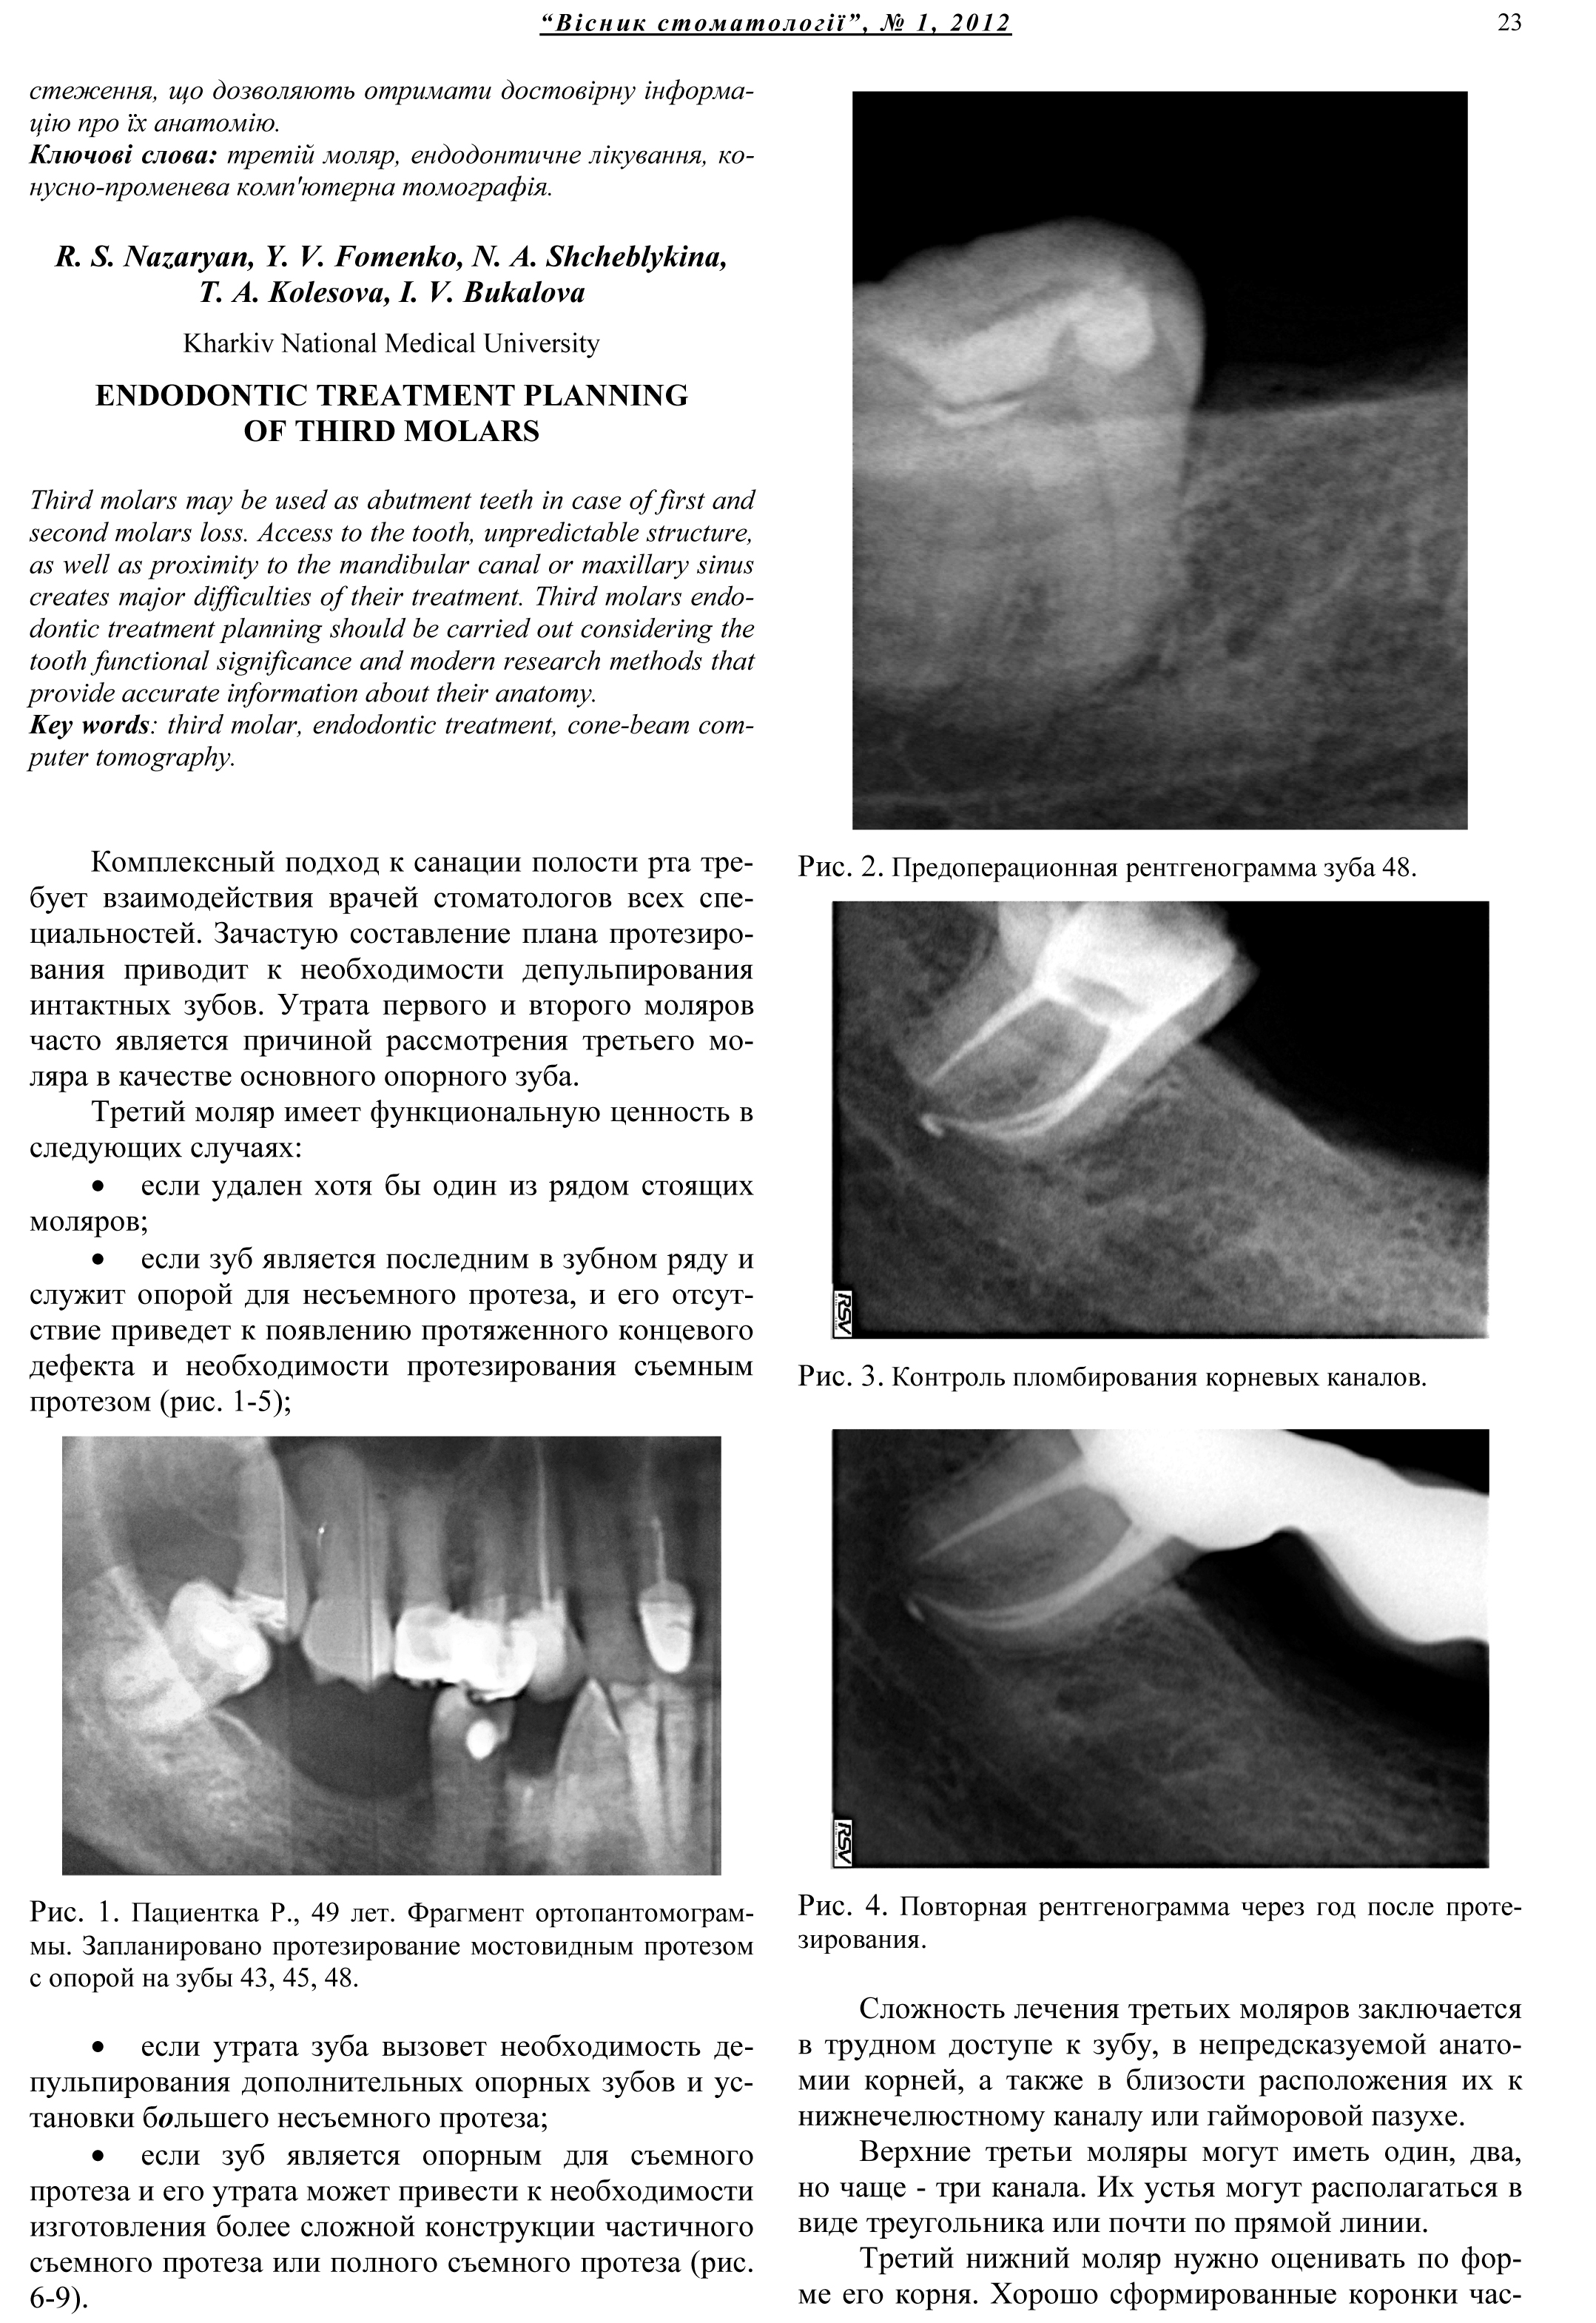

Третьи моляры возможно рассматривать в качестве опорных зубов в случае утраты первого и второго моляров. Доступ к зубу, непредсказуемое строение, а так же близость к нижнечелюстному каналу или гайморовой пазухе создают основные сложности при их лечении. Планирование эндодонтического лечения третьих моляров необходимо проводить с учетом функциональной ценности зуба и данных современных методов обследования, позволяющих получить достоверную информацию об их анатомии.